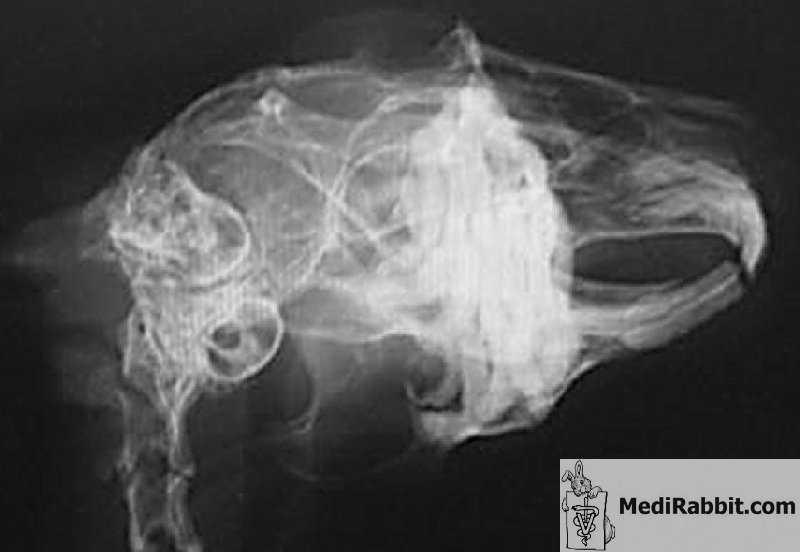

Le lapin anesthésié est immobilisé pour empêcher tout mouvement. Idéalement, des radiographies sont prises sous différents angles (ventrodorsal, latéral et oblique). Seules des images de qualité irréprochable, si possible à haute résolution, permettent d’obtenir de précieux renseignements sur les problèmes dentaires, les déformations osseuses causées par les problèmes dentaires et des informations sur les racines dentaires, la présence d’abcès, l’extension des dommages au niveau de l’os. Des prises de vues effectuées par tomographie (CT scan) permettent d’affiner la diagnose, de localiser précisément un abcès et d’évaluer si le traitement envisagé permet d’obtenir un résultat satisfaisant pour le lapin.

Vue latérale droite (gauche) et ventro-dorsale (droite) du crâne d’un lapin nain présentant des anormalités dentaires au niveau des incisives et des molaires.